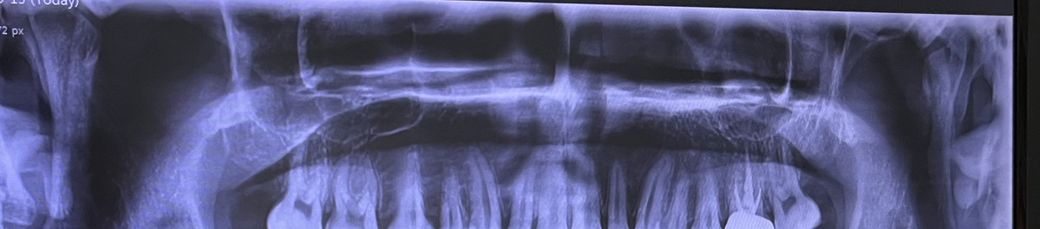

치과에서 상담받기위해 찍은 사진입니다 예전에는 턱관절이 좀 아팠는데 1년있으니까 괜찮아졌거 요새는 입을 벌릴 때 힘들거나 통증은 따로없고 소리도 거의 나지 않습니다. 근데 제가 잘 때 이갈이 하는 버릇이 있어서 걱정돼서 올립니다. 의사쌤이 괜찮다고는 하셨는데 그래도 걱정돼서 ㅠ ㅠ..

상기 X선 사진으로는 턱관절이 보이지 않습니다.

턱관절은 더 아래에 존재합니다.

현재 사진은 턱관절을 보기 위한 엑스레이이기 보다는 치아 및 잇몸을 한꺼번에 파악하기 위한 엑스레이 사진일 가능성이 있습니다. 턱관절에 대해 진료를 하기 위해서는 의사의 이학적 검사가 우선되어야 하며 턱관절 엑스레이가 도움이 될 수는 있으나 골절 등의 소견이 없다면 유용성에 한계가 있습니다.

• 아쉽지만 올리신 파노라마 사진에는 턱관절이 보이지 않기 때문에 평가를 하기가 어렵습니다. 또한 관절 부위는 단순 방사선 사진으로는 자세하게 관찰하기 어렵기 때문에 상태 파악을 위해서는 MRI 등의 정밀 검사가 필요할 것으로 사료됩니다.

그리고 엑스레이상 턱관절이 보이지 않습니다.